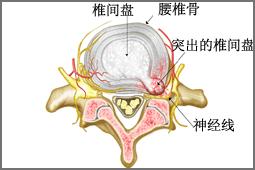

腰间盘突出症状结构解剖图

腰间盘突出症状结构解剖图